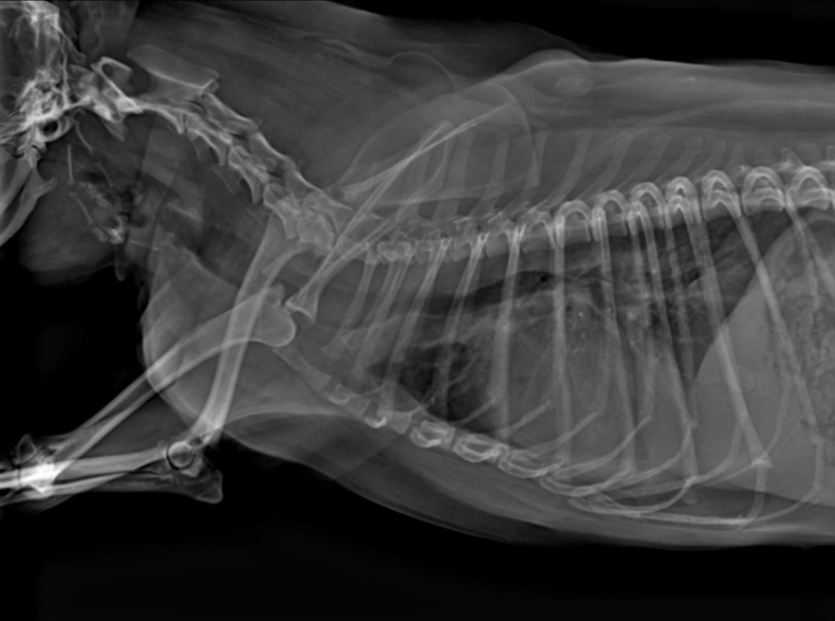

기침에 대한 원인을 감별하기 위하여 신체검사와 함께 우선 흉부방사선 사진을 촬영하였습니다. 신체검사의 청진상 중등도의 심잡음이 확인되었으며, 방사선상 기관의 불규칙한 주행이 확인되었습니다. 폐도 초기 폐수종을 고려해야하는 폐침윤 패턴이 관찰되었습니다.

또한 심장의 크기를 간접적으로 측정할 수 있는 VHS를 이용하여 보았을 때, VHS가 11.2로 품종별 차이를 고려하더라도 태리의 심장은 다소 크게 관찰되었습니다.

초음파 검사상 태리는 이첨판막의 변성과 더불어 중등도 이상의 역류가 확인되었으며, 좌심방과 좌심실의 확장 정도가 정상 상한치 정도의 수준으로 진행된 것을 확인하였습니다.

이에 따라 폐에서 관찰된 폐침윤은 심인성 폐수종의 가능성이 높게 판단되어 이에 맞는 적절한 약물 처치와 함께 산소 공급, 패치 부탁 등의 치료가 시작되었습니다.